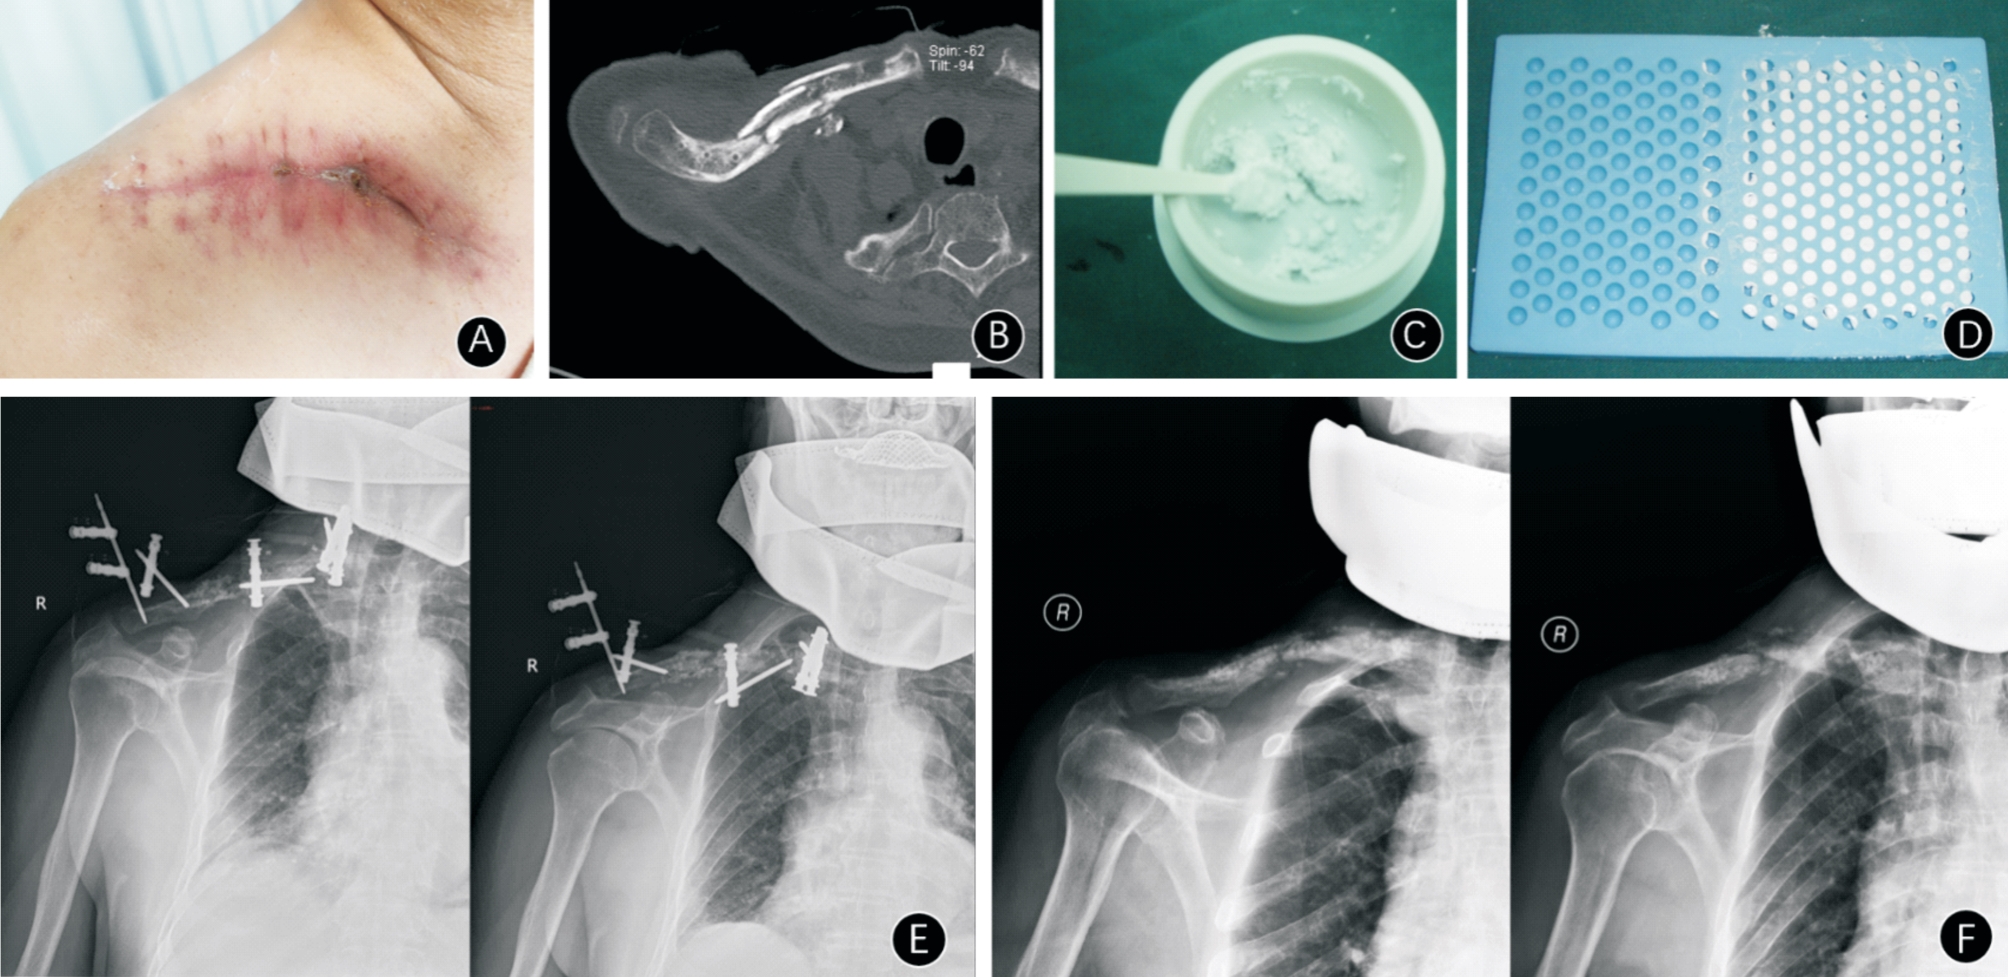

目的 探讨病灶清除联合载抗生素人工骨治疗锁骨骨髓炎的疗效。 方法 回顾性分析2012年1月至2022年6月河南省洛阳正骨医院(河南省骨科医院)收治的45例锁骨骨髓炎患者资料。根据手术方法不同分为两组,观察组(n = 24)采用病灶清除联合载抗生素人工骨植入术;对照组(n = 21)采用病灶清除术。比较两组患者手术时间、引流管放置时间和伤口愈合时间,术前及术后14 d白细胞(WBC)、C反应蛋白(CRP)、红细胞沉降率(ESR)等血清炎性指标控制情况,术前与术后1个月视觉模拟评分(VAS)及术后12个月Constant肩关节功能评分,随访有无感染复发及并发症发生情况。 结果 45例患者均顺利进行手术,均获随访13 ~ 35个月,平均(23.53 ± 5.11)个月。两组患者治疗情况比较,观察组的手术时间和引流管放置时间均长于对照组(P < 0.05),伤口愈合时间比较差异无统计学意义(P > 0.05);两组术前与术后14 d的WBC、CRP、ESR血清炎性指标、术后1个月视觉模拟评分(VAS)和术后12个月Constant肩关节功能评分比较均显著改善,差异均有统计学意义(P < 0.05),且观察组Constant肩关节功能评分优于对照组(P < 0.05)。随访过程中,观察组2例(8.33%)感染复发,优于对照组5例(23.81%);观察组2例出现无菌性渗出并发症;观察组1例骨缺损不愈合,对照组5例,经二期髂骨植骨后骨缺损均愈合,余均未出现无菌性渗出、骨缺损和病理性骨折并发症。 结论 病灶清除联合载抗生素人工骨治疗锁骨骨髓炎可有效控制感染,保留锁骨的外形与功能,降低术后感染复发率,手术操作简单,且无严重并发症,值得临床推广。